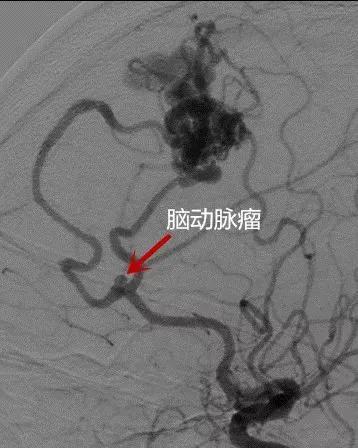

脑出血手术 竟然藏着两颗“炸弹”

在这场手术中,医生们面临着两大“炸弹”:一是术中再出血,二是术后并发症。术中再出血是脑出血手术中最令人恐惧的意外之一。由于脑内组织结构复杂,血管构成繁多,即使经验丰富的医生也难以完全避免这一风险。一旦发生再出血,不仅会增加手术难度,还可能危及患者生命。